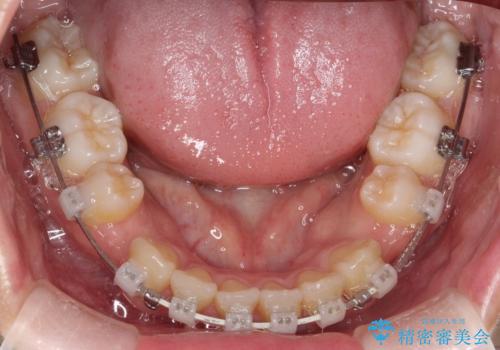

ワイヤーによる抜歯矯正でガタガタの改善

- 前歯のがたがたを主訴に来院されました。

上下の前歯が前方に傾斜しているのもあり、内側に前歯をひっこめるために上下左右の歯を1本ずつ抜歯して矯正することとしました。

ガタガタも改善しましたが、前歯が内側に引っ込むことにより口元もすっきりして、唇が閉じやすくなりました。